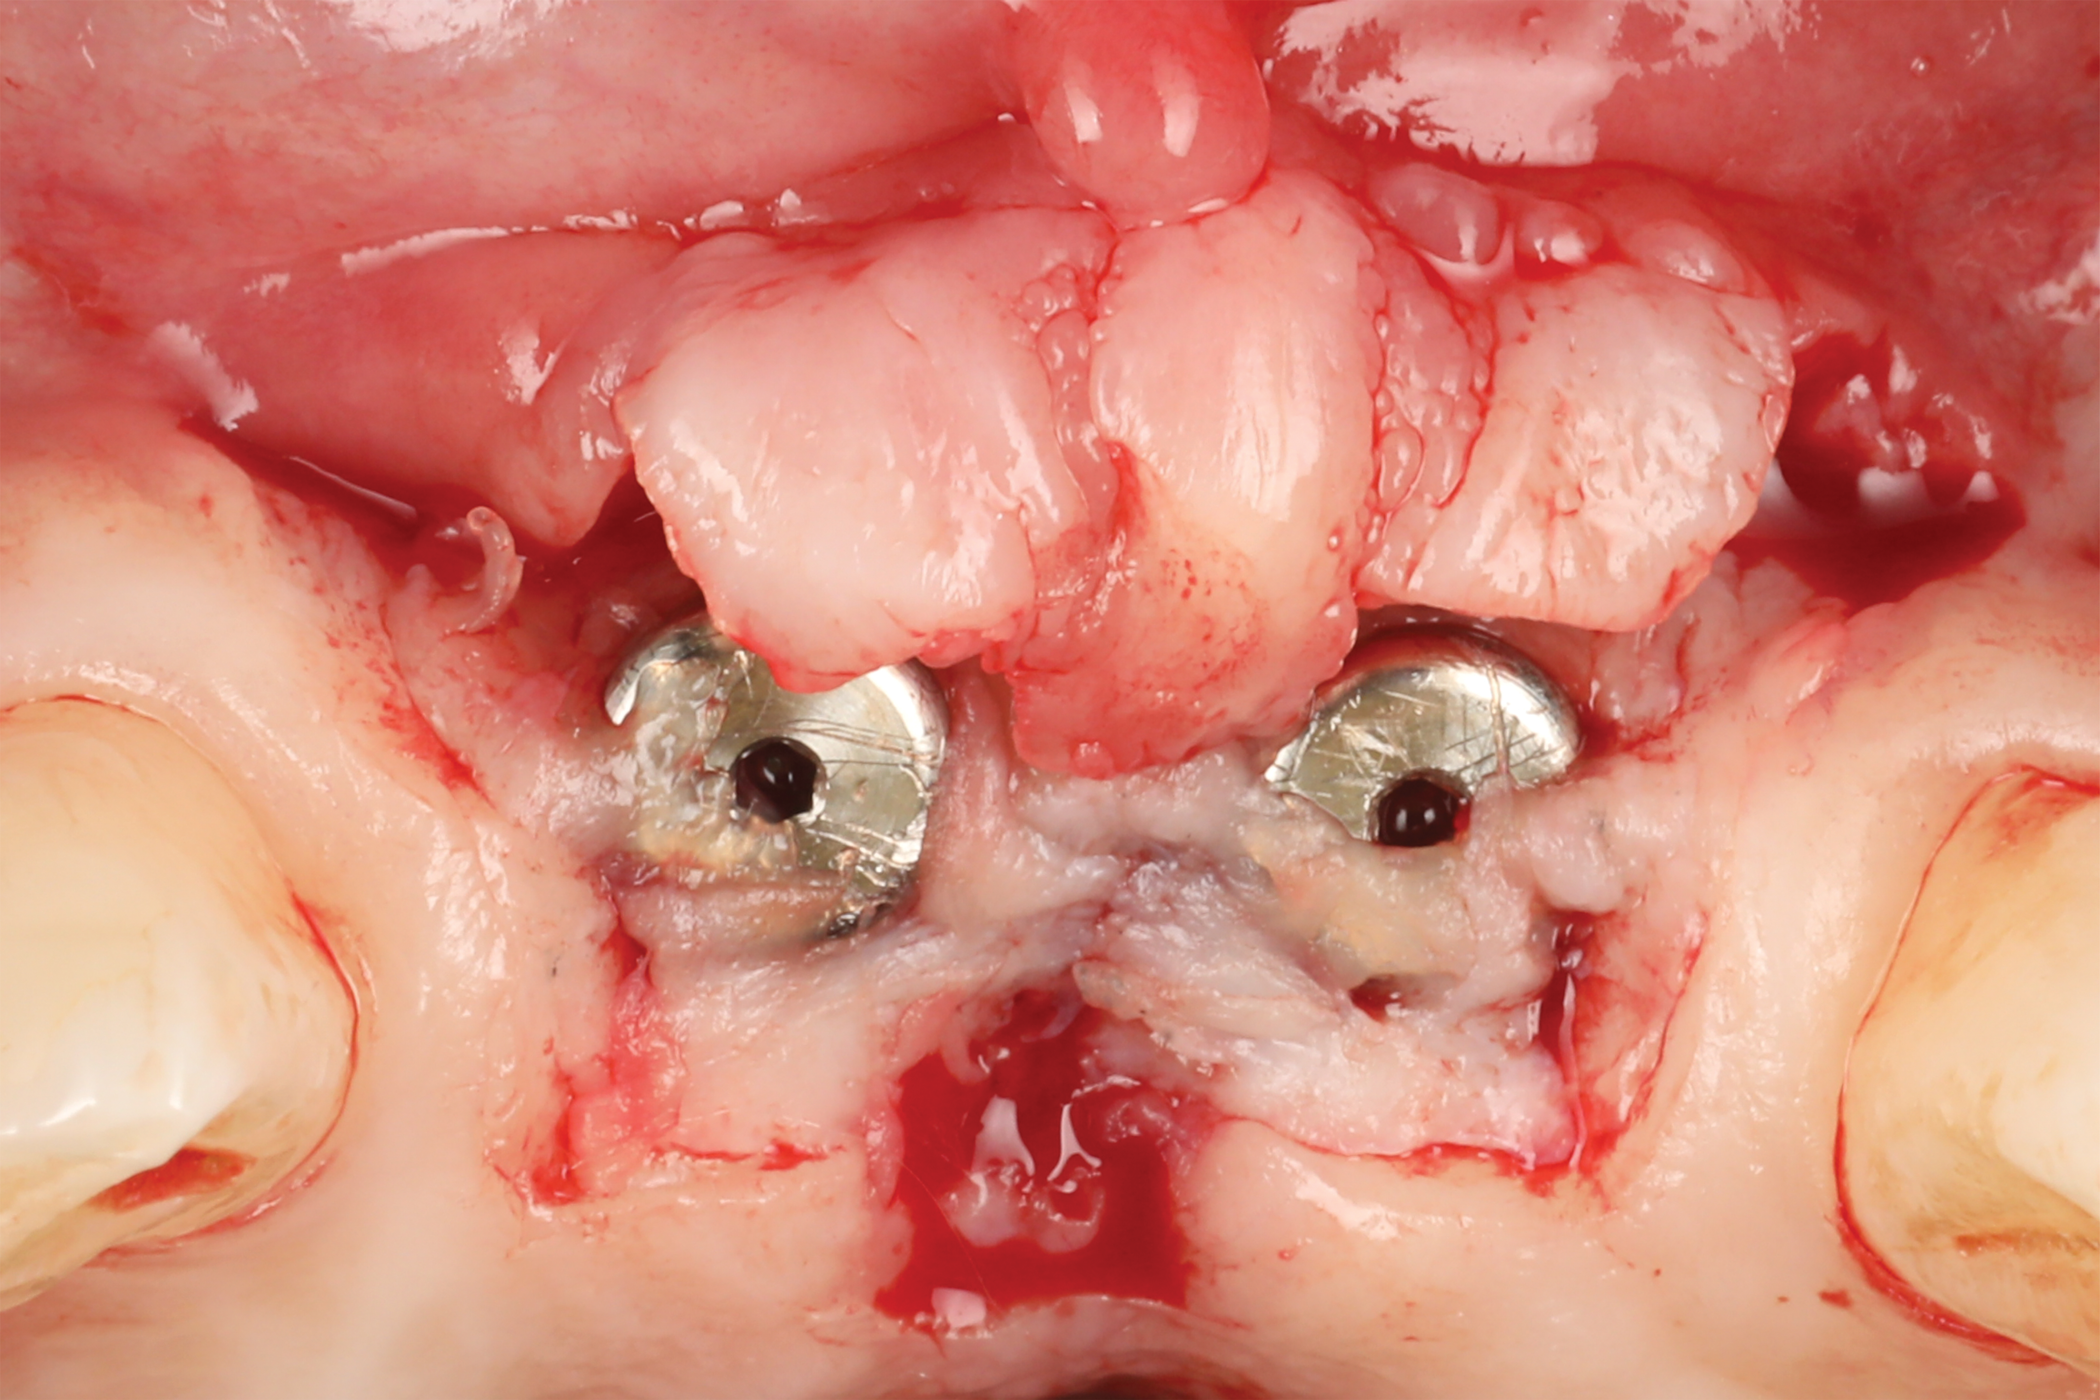

Fig 1. Clinical view at presentation.

Figure 1

A 46-year-old systemically and periodontally healthy woman presented to the Graduate Periodontics Clinic at the University of Michigan School of Dentistry with the chief complaint of poor esthetics of her smile due to two dental implants (Nos. 8 and 9) showing their metal components (Figure 1). The patient reported that the implants had been placed 15 to 20 years previously after an accident. Clinical examination revealed that the implants had probing depths within 3 mm (facial probing depth of 3-2-3 mm for implant No. 8 and 2-2-2 mm for implant No. 9), no bleeding on probing, and no suppuration; the implants were therefore diagnosed as healthy (Figure 1 and Figure 2). The papilla between the two implants was deficient on the buccal aspect. The implants were buccally positioned, and a substantial lack of soft-tissue volume was noted.

After 3 months of submerged healing, the operated area presented with limited keratinized mucosa on the buccal aspect (Figure 8). Therefore, a flap with two vertical incisions was designed starting from the palatal aspect of the two submerged implants. In addition, the mid-palatal portion of the flap was further extended toward the palatal aspect to obtain a roll flap that was de-epithelialized with a bur and eventually rolled to increase the interproximal soft tissue between the two implants (Figure 9). The flap was elevated in split-thickness fashion, with the soft tissue on top of the implants being removed to identify the cover screws (Figure 10). A substantial increase in soft-tissue thickness was observed at the buccal aspect of the implants compared to the first surgical procedure (Figure 11), when the implant fixtures were visible through a thin layer of connective tissue fibers adherent to the implant surfaces. The cover screws were removed, and temporary titanium abutments were connected.